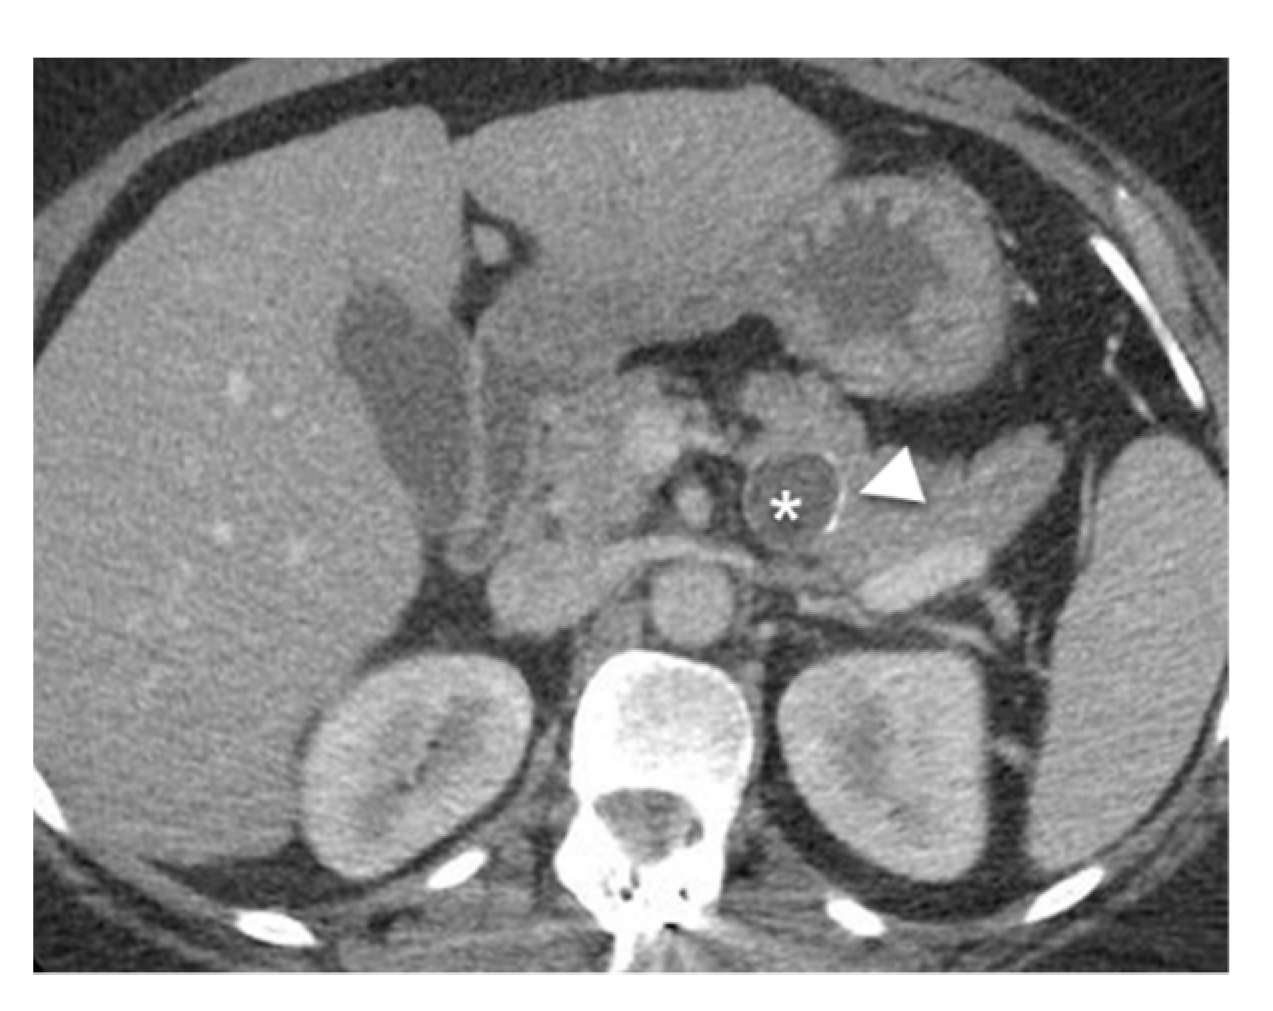

- Mamone, G.; Barresi, L.; Tropea, A.; Di Piazza, A.; Miraglia, R. MRI of mucinous pancreatic cystic lesions: A new updated morphological approach for the differential diagnosis. Updates Surg. 2020, 72, 617–637. [Google Scholar] [CrossRef] [PubMed]